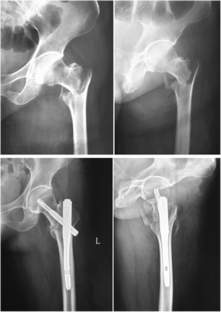

Fig. 1